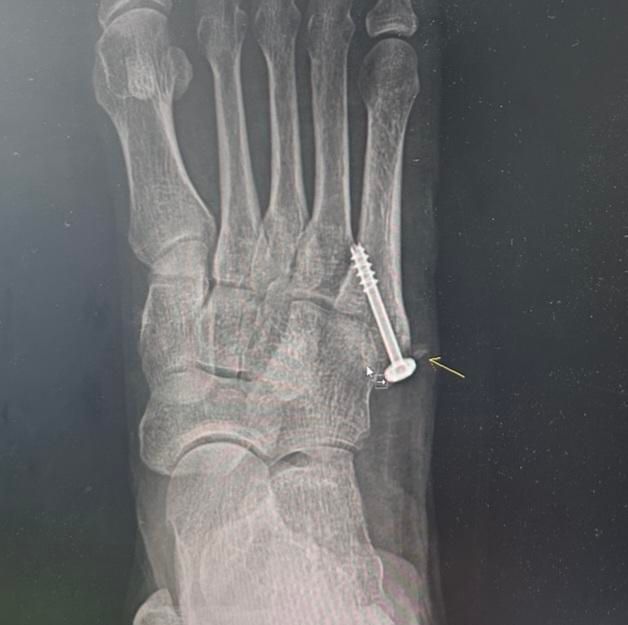

어머니께서 약 2주전 새끼발가락-발등 부근을 수술하셨습니다. 첨부한 x레이 사진처럼 수술하였는데 상처 염증등으로 실밥을 풀지 못해 퇴원이 미뤄지던 중 요근래 호전되어 내일모레쯤 실밥을 풀고 퇴원할 예정이었으나 갑자기 수술 엑스레이를 보여주며 사진의 화살표 표시한 부분처럼 뼛조각이 남아있는걸 이제 알았고, 약 1년 뒤 나사를 빼며 제거해주겠다고 합니다.

그 뼛조각이 아예 떨어져나가있는 것인지 발가락 뼈에 약간 붙어는 있는 것인지 병원측에서도 모르겠다고 하였는데 이를 1년간 그대로 둔다면 어떤 문제가 발생할 수 있는지 궁금합니다.

• 1번 째 사진